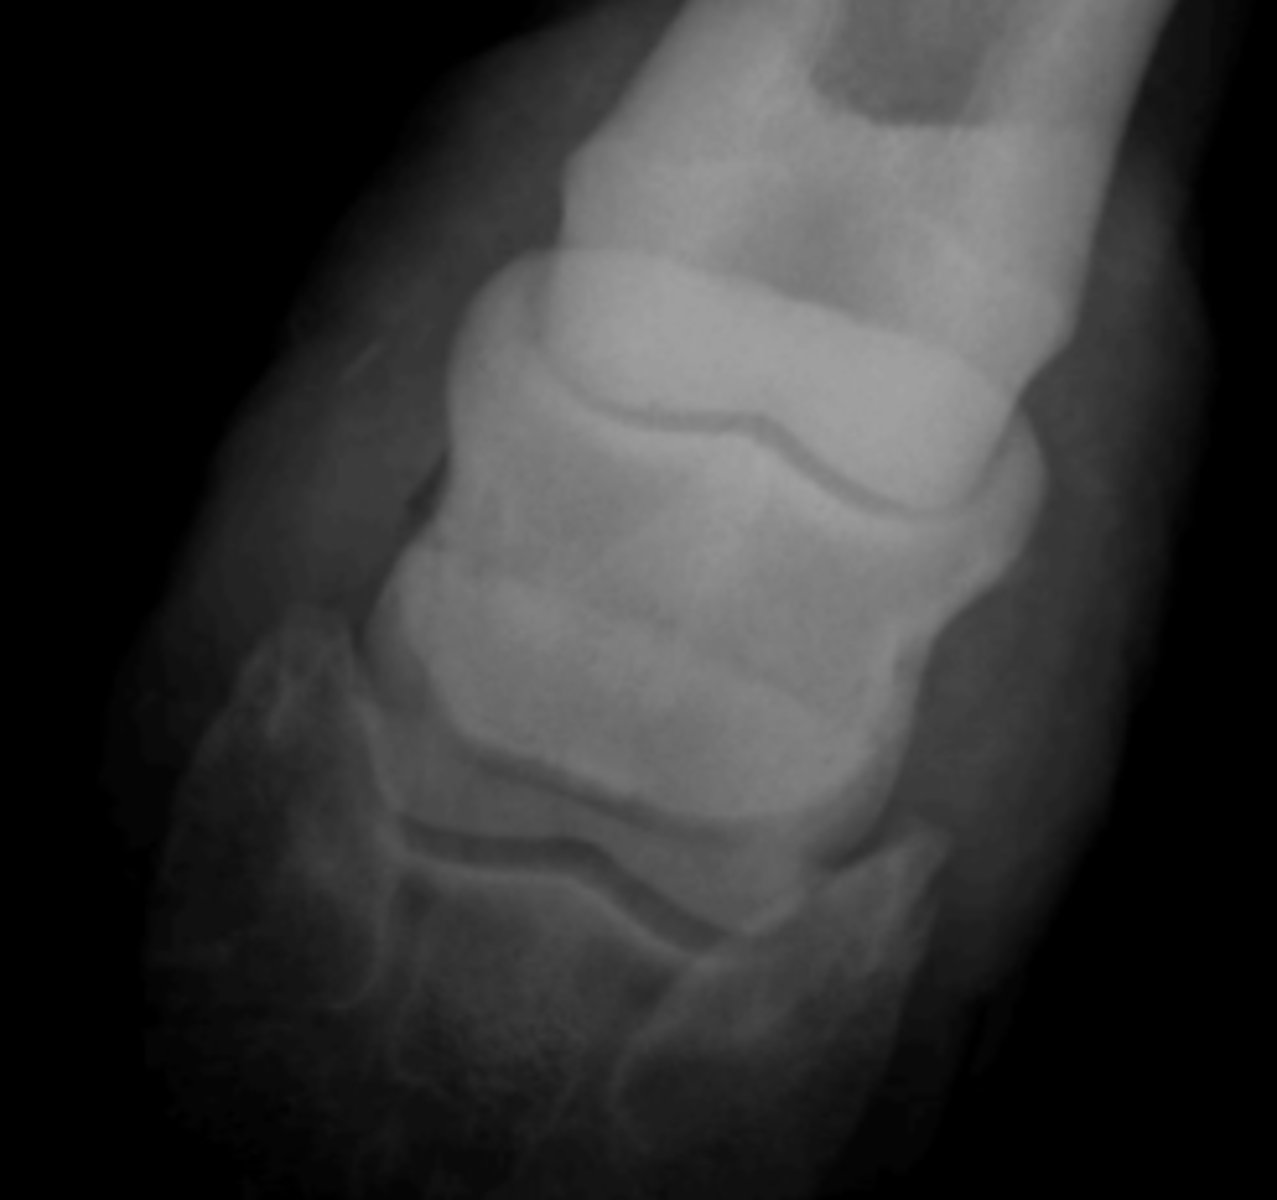

dorsopalmar oblique

Which shows the distal border of the navicular bone?

Navicular syndrome

A Horse lame in four digits- what has caused this?